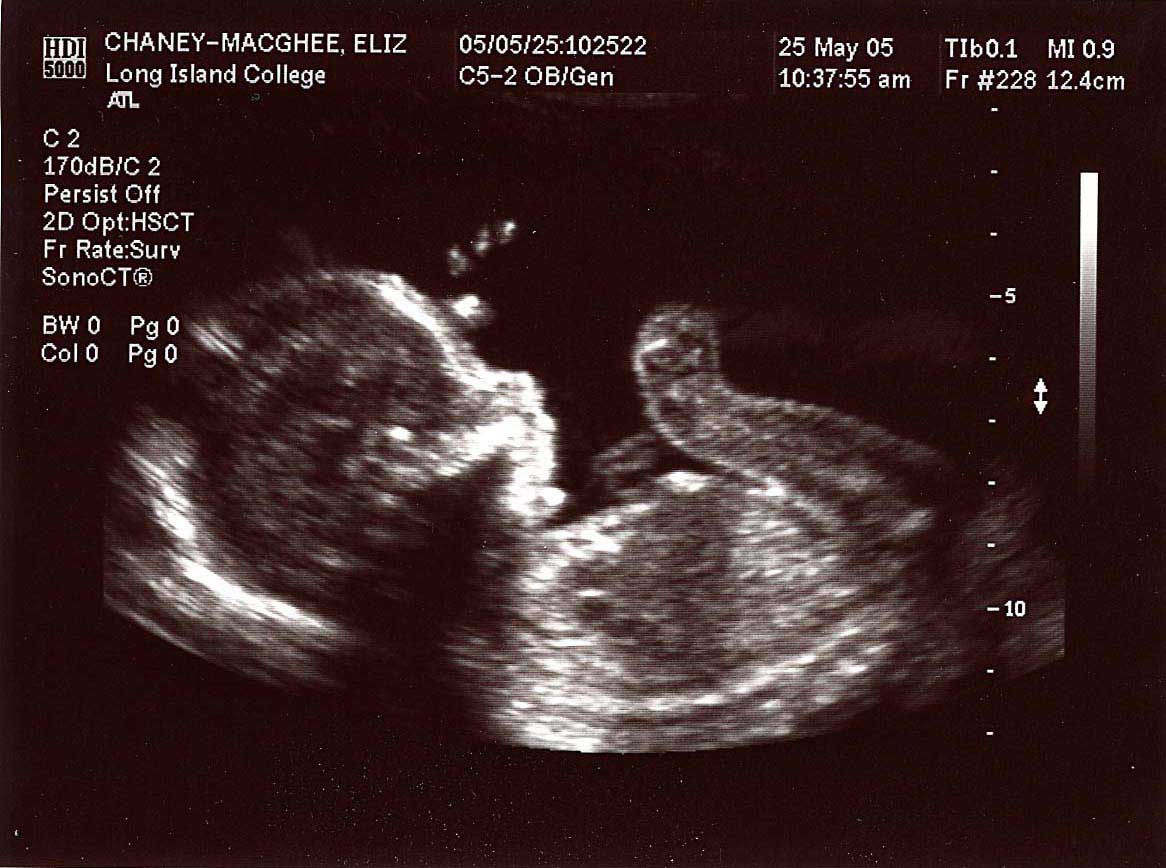

20 week series:

images taken 5/25/04, baby's weight estimated at 12 oz.

Profile at 20 weeks.